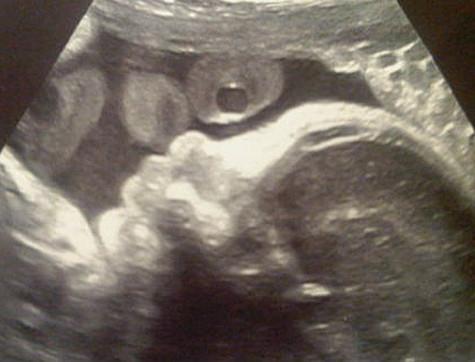

Певица Шакира и футболист Жерар Пике, в скором будущем родителями, опубликовали в Интернете первую фотографию своего будущего малыша. Исполнительница сделала УЗИ, а снимок выложила в микроблоге.

«Его портрет!» - подписала фото Шакира.

Снимок УЗИ. Фото: Twitter.com.

Отметим, что и для нее, и Жерара ребенок первым. Как ожидается, Шакира родить в следующего года. Между тем, влюбленные уже выбрали имя сыну. Пара решила назвать Биел, пишет StarHit.ru.

Напомним, что Шакира официально подтвердила, беременна, 20 сентября, на своем сайте обращение к поклонникам.